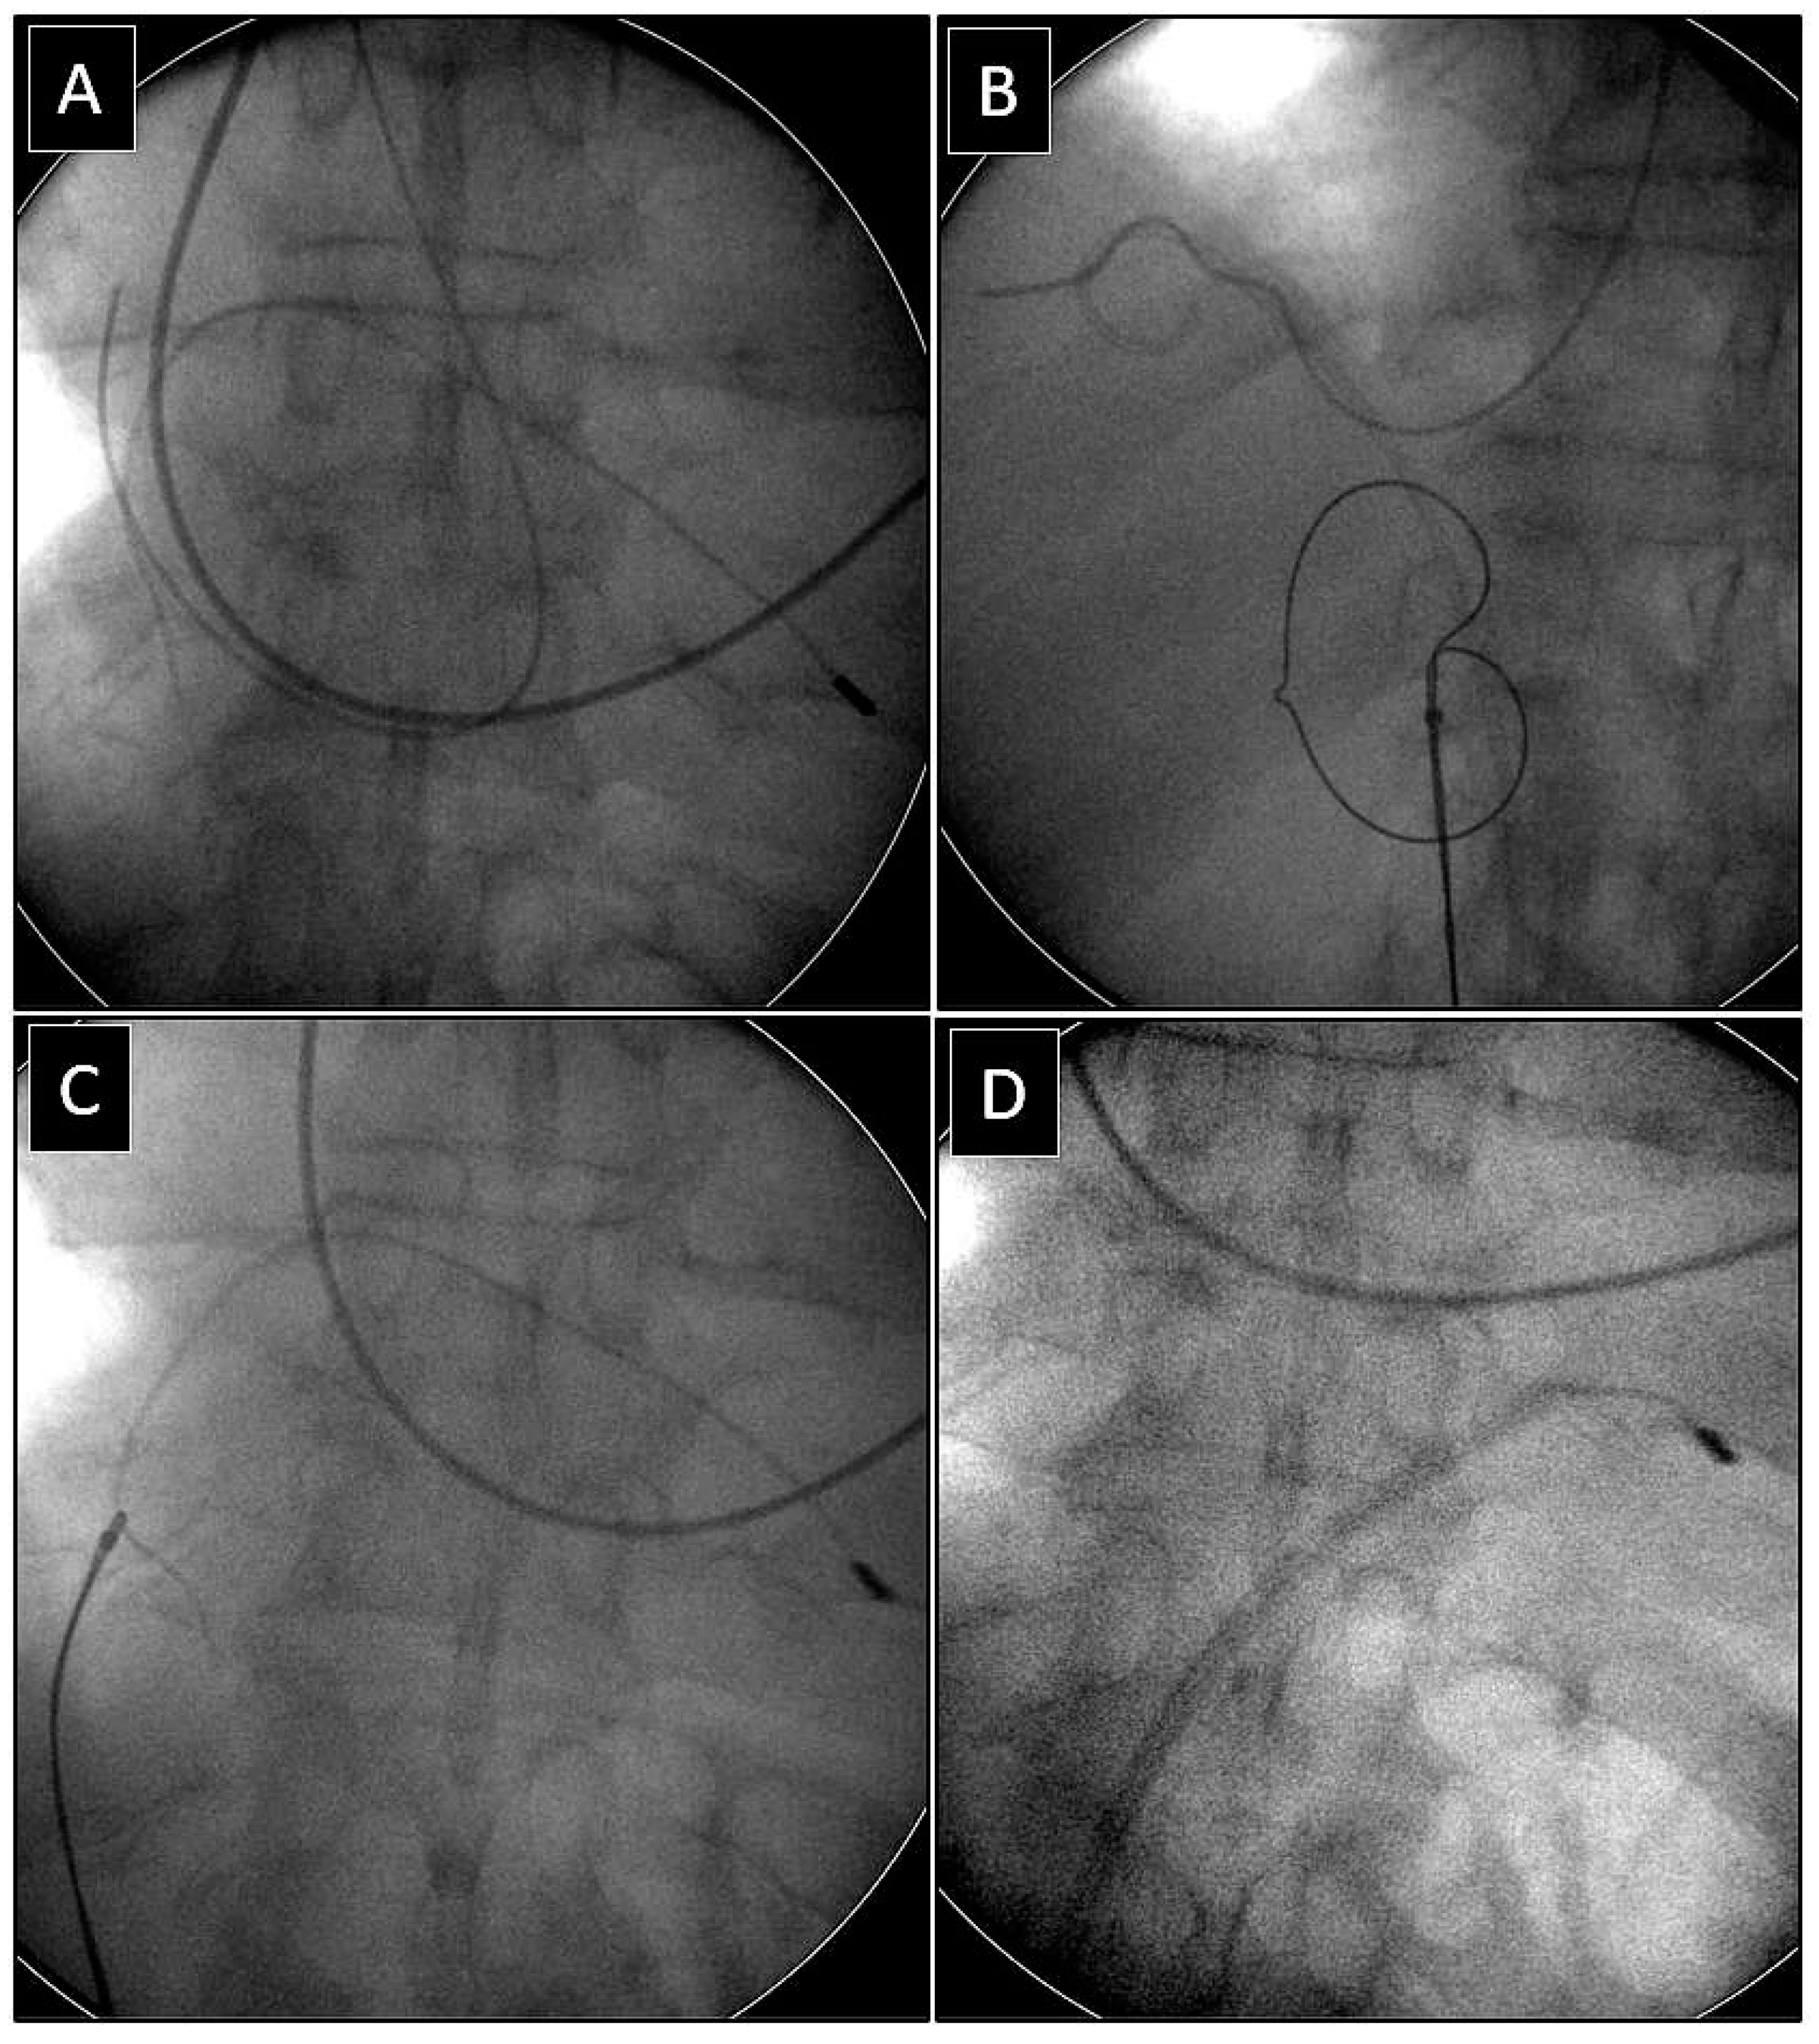

Extraction of Leads with Migrated Proximal Ends into the Cardiovascular Space

| Methods of removing fractured migrant leads | |||||

| Superior approach | 6 (15.39) | 3 (23.08) p = 0.832 | 3 (23.08) p = 0.832 | 5 (71.43) p = 0.007 | 17 (23.61) |

| Combined approach | 3 (7.69) | 3 (23.08) p = 0.316 | 1 (7.67) p = 0.548 | 1 (14.29) p = 0.874 | 8 (11.11) |

| Femoral approach | 29 (74.36) | 7 (53.85) p = 0.298 | 8 (61.54) p = 0.596 | 1 (14.29) p = 0.001 | 45 (62.50) |

| Lasso/basket in CS sheath and a polypropylene or rotational sheath over them (dilatation) | 13 (76.47) | Lasso/basket in CS sheath and a polypropylene rotational sheath over them—superior approach (dilatation) | 8 (100.0) |

| Lasso/basket in CS sheath—superior (pulling only) | 1 (5.88) | Lasso/basket in CS sheath—superior approach (pulling only) | 0 (0.00) |

| Lasso/basket only (pulling only) | 3 (17.65) | Lasso/basket only—superior approach (pulling only) | 0 (0.00) |

| Supporting tools and techniques | 17 (100.0) | Supporting tools and techniques | 8 (100.0) |

| Loop (pulling, end release) | 6 (35.29) | Loop femoral approach | 6 (75.00) |

| Pig-tail + winding and shifting superior approach (end release) | 3 (17.65) | Pig-tail femoral approach | 1 (12.50) |

| Pig-tail superior (end orientation) | 0 (0.00) | Pig-tail + winding and shifting femoral approach | 1 (12.50) |

| Not used | 8 (47.06) | Not used | 0 (0.00) |